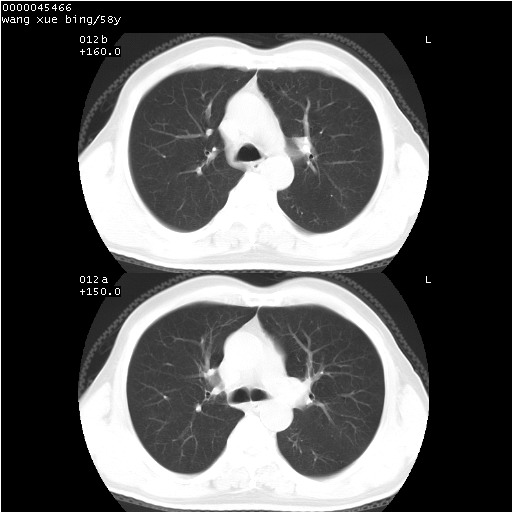

患者 男,58岁。咳嗽、咯血3月余。

胸部ct轴位平扫(层厚10mm,螺距1.5,重建间隔10mm),图像如下:

右肺下叶团块及不规则空洞,内壁不规则,外缘见粗长毛刺,临近胸膜明显增厚并与病灶关系密切。支持考虑:右肺肺脓肿!建议穿刺病理检查待除外周围型肺癌!

右肺下叶见不规则厚壁空洞,内壁不规则,外缘见粗长毛刺,临近胸膜明显增厚并与病灶关系密切。支持考虑:周围型肺癌!

右肺下叶周围型肺癌伴空洞形成!征象比较明显!分叶、毛刺、胸膜凹陷征、厚壁空洞,壁结节!

空洞壁厚,不规则,其内可见壁结节,周围可见毛刺及阻塞性炎变,多考虑癌性病变.

空洞内壁不规整,有壁结节,周围有毛刺,支持癌性空洞。